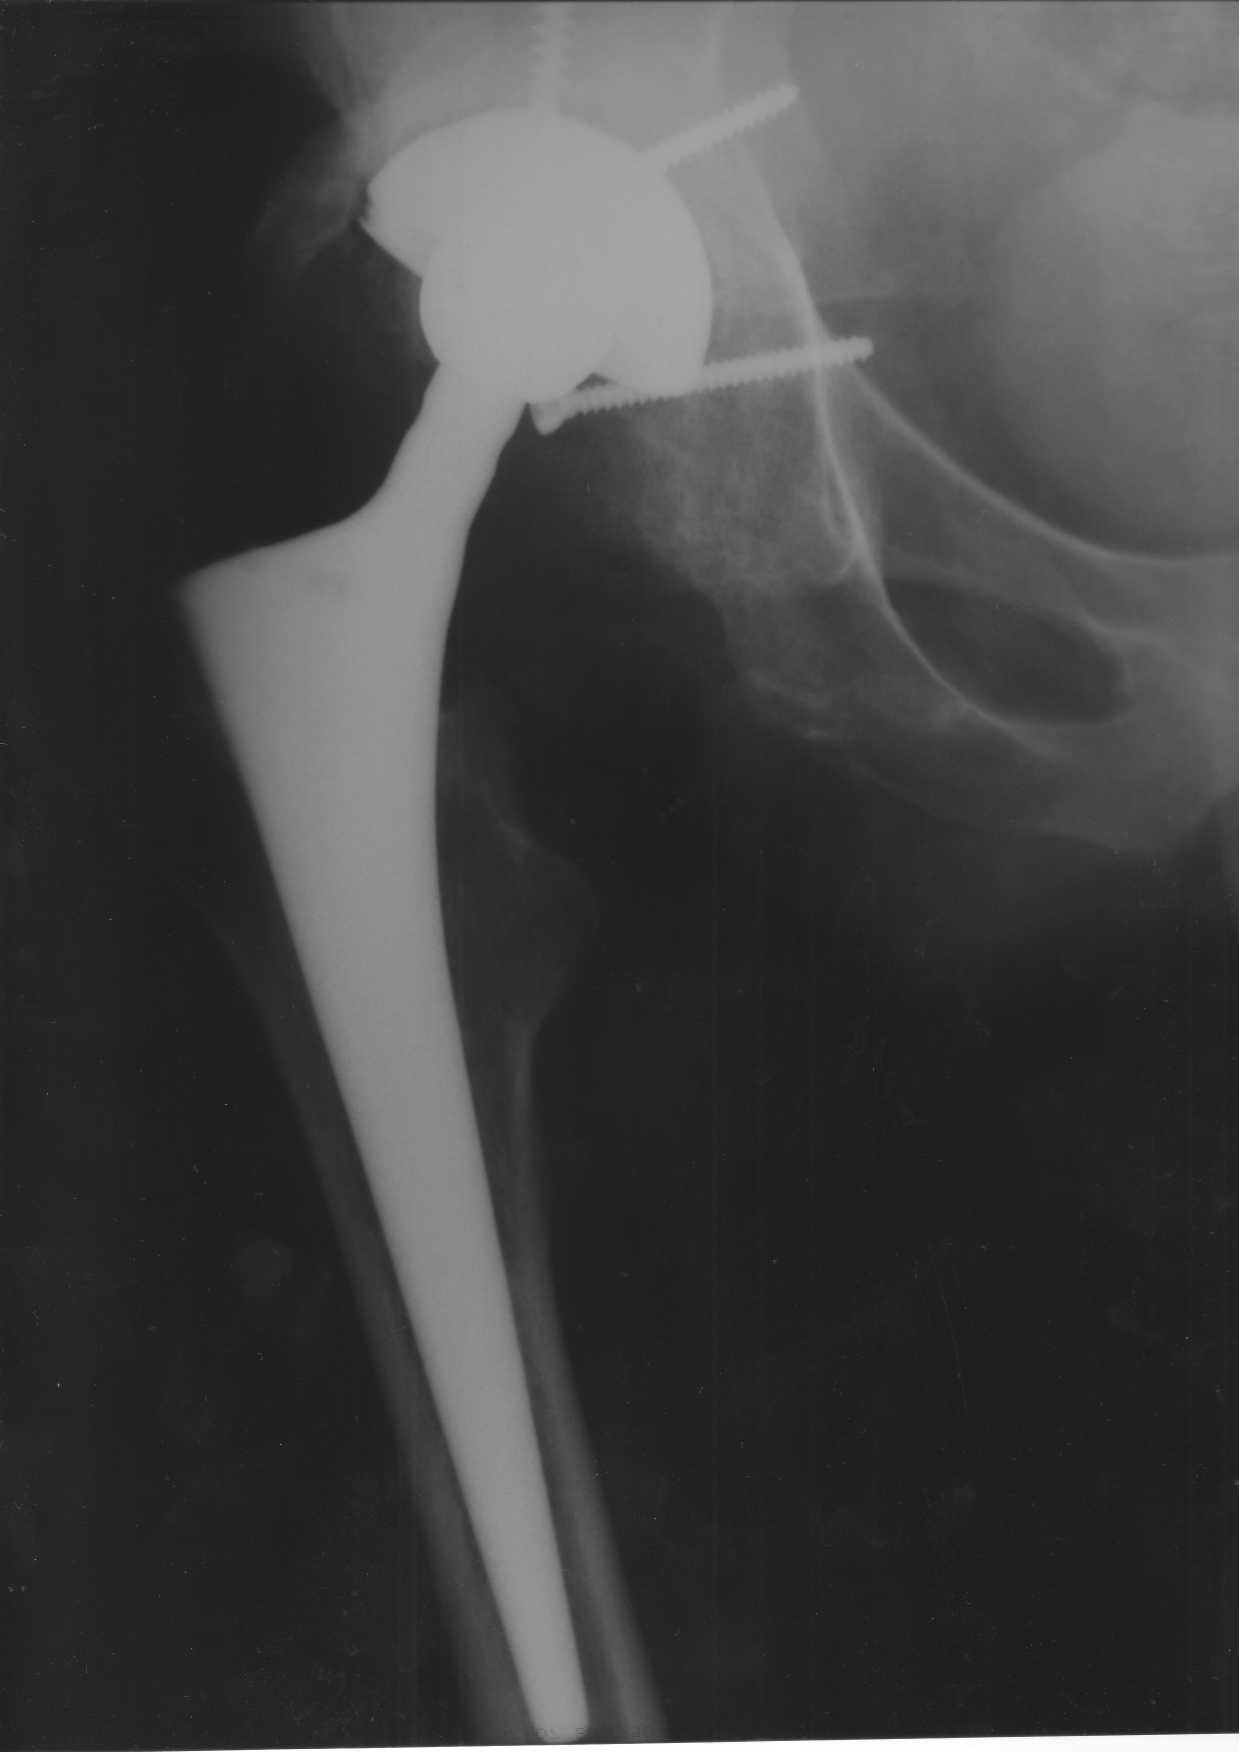

Уважаемые коллеги.В 3 Центральный Военный Клинический Госпиталь имени А. А. Вишневского, что в Красногорске, Московской области, в отделение эндопротезирования крупных суставов поступил пациент 1960 года рождения Жалобы при поступлении: на боли в области левого тазобедренного сустава (больной указывает на точку расположенная в середине условной линии между седалищным бугром и большим вертелом), усиливающиеся в начале ходьбы, при опоре на левую ногу с иррадиацией болей по наружной и наружно-задней поверхности левого бедра, левый коленный сустав; снижение объема движения в левом тазобедренном суставе, снижение опорной способности левой нижней конечности, хромоту на левую ногу, необходимость использования дополнительной опоры (костыли) при ходьбе, снижение объема двигательной активности из за болей в суставе.В анамнезе: Со слов больного, согласно медицинских документов, в 1989 году получил травму левой нижней конечности: закрытый перелом левой вертлужной впадины с центральным вывихом головки левой бедренной кости. Лечился консервативное. В процессе лечения сформировался посттравматический артроз, укорочение левой нижней конечности до 5 см. 25.04.2005 года в Подольском Окружном Госпитале Министерства Обороны выполнено: одномоменто, остеосинтез заднего края вертлужной впадины фрагментом резецированной головки бедренной кости и тотальное эндопротезирование левого тазобедренного сустава бесцементным эндопротезом "VERSIS ET" с бесцементной чашкой TRILOGY. Послеоперационный период осложнился ранним нагноением области эндопротеза, в результате санаций очага инфекции и антибиотикотерапии, активного промывного дренирования антисептиками, послеоперационная рана зажила. После операции, со слов больного, через два месяца в полном объеме стал нагружать левую нижнюю конечность. В течение полгода, после операции чувствовал себя вполне удовлетворительно. С марта 2006года стал отмечать появление болей в области тазобедренного сустава, то в области паха, то в области левой ягодицы. С августа месяца отмечает те жалобы, с которыми он сейчас к нам обратился. Температура тела, после заживления раны, нормальная. В анализах крови, лейкоциты около 7 тыс, формула нормальная, СОЭ 12 мм ч. Локально: при осмотре обеих нижних конечностей, анатомическая ось конечности не нарушена; отмечено относительное укорочение левой н\конечности на 1.5 см., гипотрофия мышц левого бедра 3 см, голени 2 см, симптом. Объем движений в тазобедренных суставах: правый~ сгибание- 60 гр, разгибание-180 гр ,отведение- 35 гр, левый~ сгибание- 110 гр , разгибание-170 гр , отведение-15 гр. Контуры других суставов н/конечностей обычные, объем движений в них не страдает. Пульсация на артериях конечностей удовлетворительная. Неврологические нарушения конечностей отсутствуют, рефлексы на обеих н/конечностях одинаковые, чувствительных нарушений нет. Осевая нагрузка на левую нижнюю конечность вызывает боль в точке расположенная в середине условной линии между седалищным бугром и большим вертелом. Отмечается пигментация и пастозность нижней трети обеих голеней и стоп, характерная для посттромботической болезни. На Цветном дуплексном сканировании сосудов нижних конечностей: Нестенозирующий атеросклероз обеих бедренных и подколенных артерий . Гемодинамически значимых препятствий кровотоку в магистральных артериях ног не выявлено. Глубокие и поверхностные вены нижних конечностей проходимы. Умеренная недостаточность клапанов подколенных вен. Данных за тромбоз глубоких вен на момент осмотра не получено.А вот что пишет наш рентгенолог: На серии рентгенограмм области левого тазобедренного сустава определяется тотальный бесцементный эндопротез. Вокруг тени чашки эндопротеза определяется ободок остеорезорбции. Кроме того, визуализируется деформированный костный винт фиксирующий консолидированный отломок вертлужной впадины, вплотную прилегающий к тени чашки эндопротеза. Заключение: Рентгеновские признаки нестабильности чашки тотального эндопротеза. Лучевая нагрузка: 6 мЗв. У нас в отделении разошлись мнения: начальник мой утверждает, после сравнения снимков, принесенных больным от августа и октября 2006года и наших рентгенснимков, что у больного нет нестабильности вертлужного компонента, и что надо назначит курс консервативной терапии: препараты кальция, миакальцик, увеличить осевую нагрузку на левую нижнюю конечность, ЛФК направления на укрепление мышц бедра, ягодиц, физиолечение. А я утверждаю, что у больного клиника нестабильности вертлужного компонента, и необходима ревизия вертлужного компонента, не исключено даже наличие инфекции под чашкой эндопротеза (не смотря на отсутствие клинических признаков инфекции). В результате проводимой консервативной терапии, боли у больного усилились. Помогите рассудить нас, мы готовы выслушать ваши мнения по этому поводу. С уважением Батал Шушания.3 ЦВКГ имени А. А. Вишневского

Ув. Коллега.Четких рентгенологических признаков нестабильности вертлужного компонента действительно нет. Здесь, кроме нестабильности, можно искать причину в поясничный отдел позвоночника(Hip-spain синдром - всё-таки 15 лет ходил с укорочением),либо сделать спиральный КТ и посмотреть, нет ли несращения в области старого перлома вертлужной впадины. Зачастую ложные суставы подвздошной, седалищной, а иногда и лонной костей являются причинами несостоятельности эндопротезов.

Уважаемый д-р Батал,

Ситуация не столь однозначная как Вам это видится. По подробно описываемой клинике с большей вероятностью речь идет о проблемах

поясничного отдела позвоночника. Есть зона остеолиза вокруг чашки, но как правило, дополнительный винт держит чашку достаточно хорошо, и даже при наличии микроподвижности, это не сопровождается столь ярким болевым синдромом. Поэтому, я бы сделал следующее: МРТ позвоночника, пункцию ТБС для исключения инфекционного процесса. Ревизию рассматривал бы как крайний вариант, учитывая выполненную костную пластику и отсутствие явных признаков нестабильности.

уважаемый коллега, Антон Вакуленко. Спасибо за четкий, расписанный по пунктам план действий. При поступлении пациента в отделение, я думал точно как вы. Но на следующий день, выполнил многопроеционное рентгенисследование, показал невропатологу, и доложил начальнику отделения о больном.После разбора пришли к следующему, да у больного действительно нестабильность вертлужного компонента, есть зона лизиса в месте костного аутотрансплантата, а в месте фиксаци чашки деротационным винтом четко выраженный контакт чашки с костной тканю. Мы пришли к выводу,что лизис костного аутотрансплантата из за осевой перегрузки на фоне незавершенного ремоделирования (вес больного 130 кг). Потому мы и приняли план вышеуказанного лечения. Провели беседу с больным, больной согласился с нами. Через 3-6 месяцев мы оценим эффективность лечения и доложу. Возможно и придется тогда идти на ревизию с заменой только вертлужного компонента а может и придется удалить весь эндопротез с установкой спейсера.. посмотрим.....